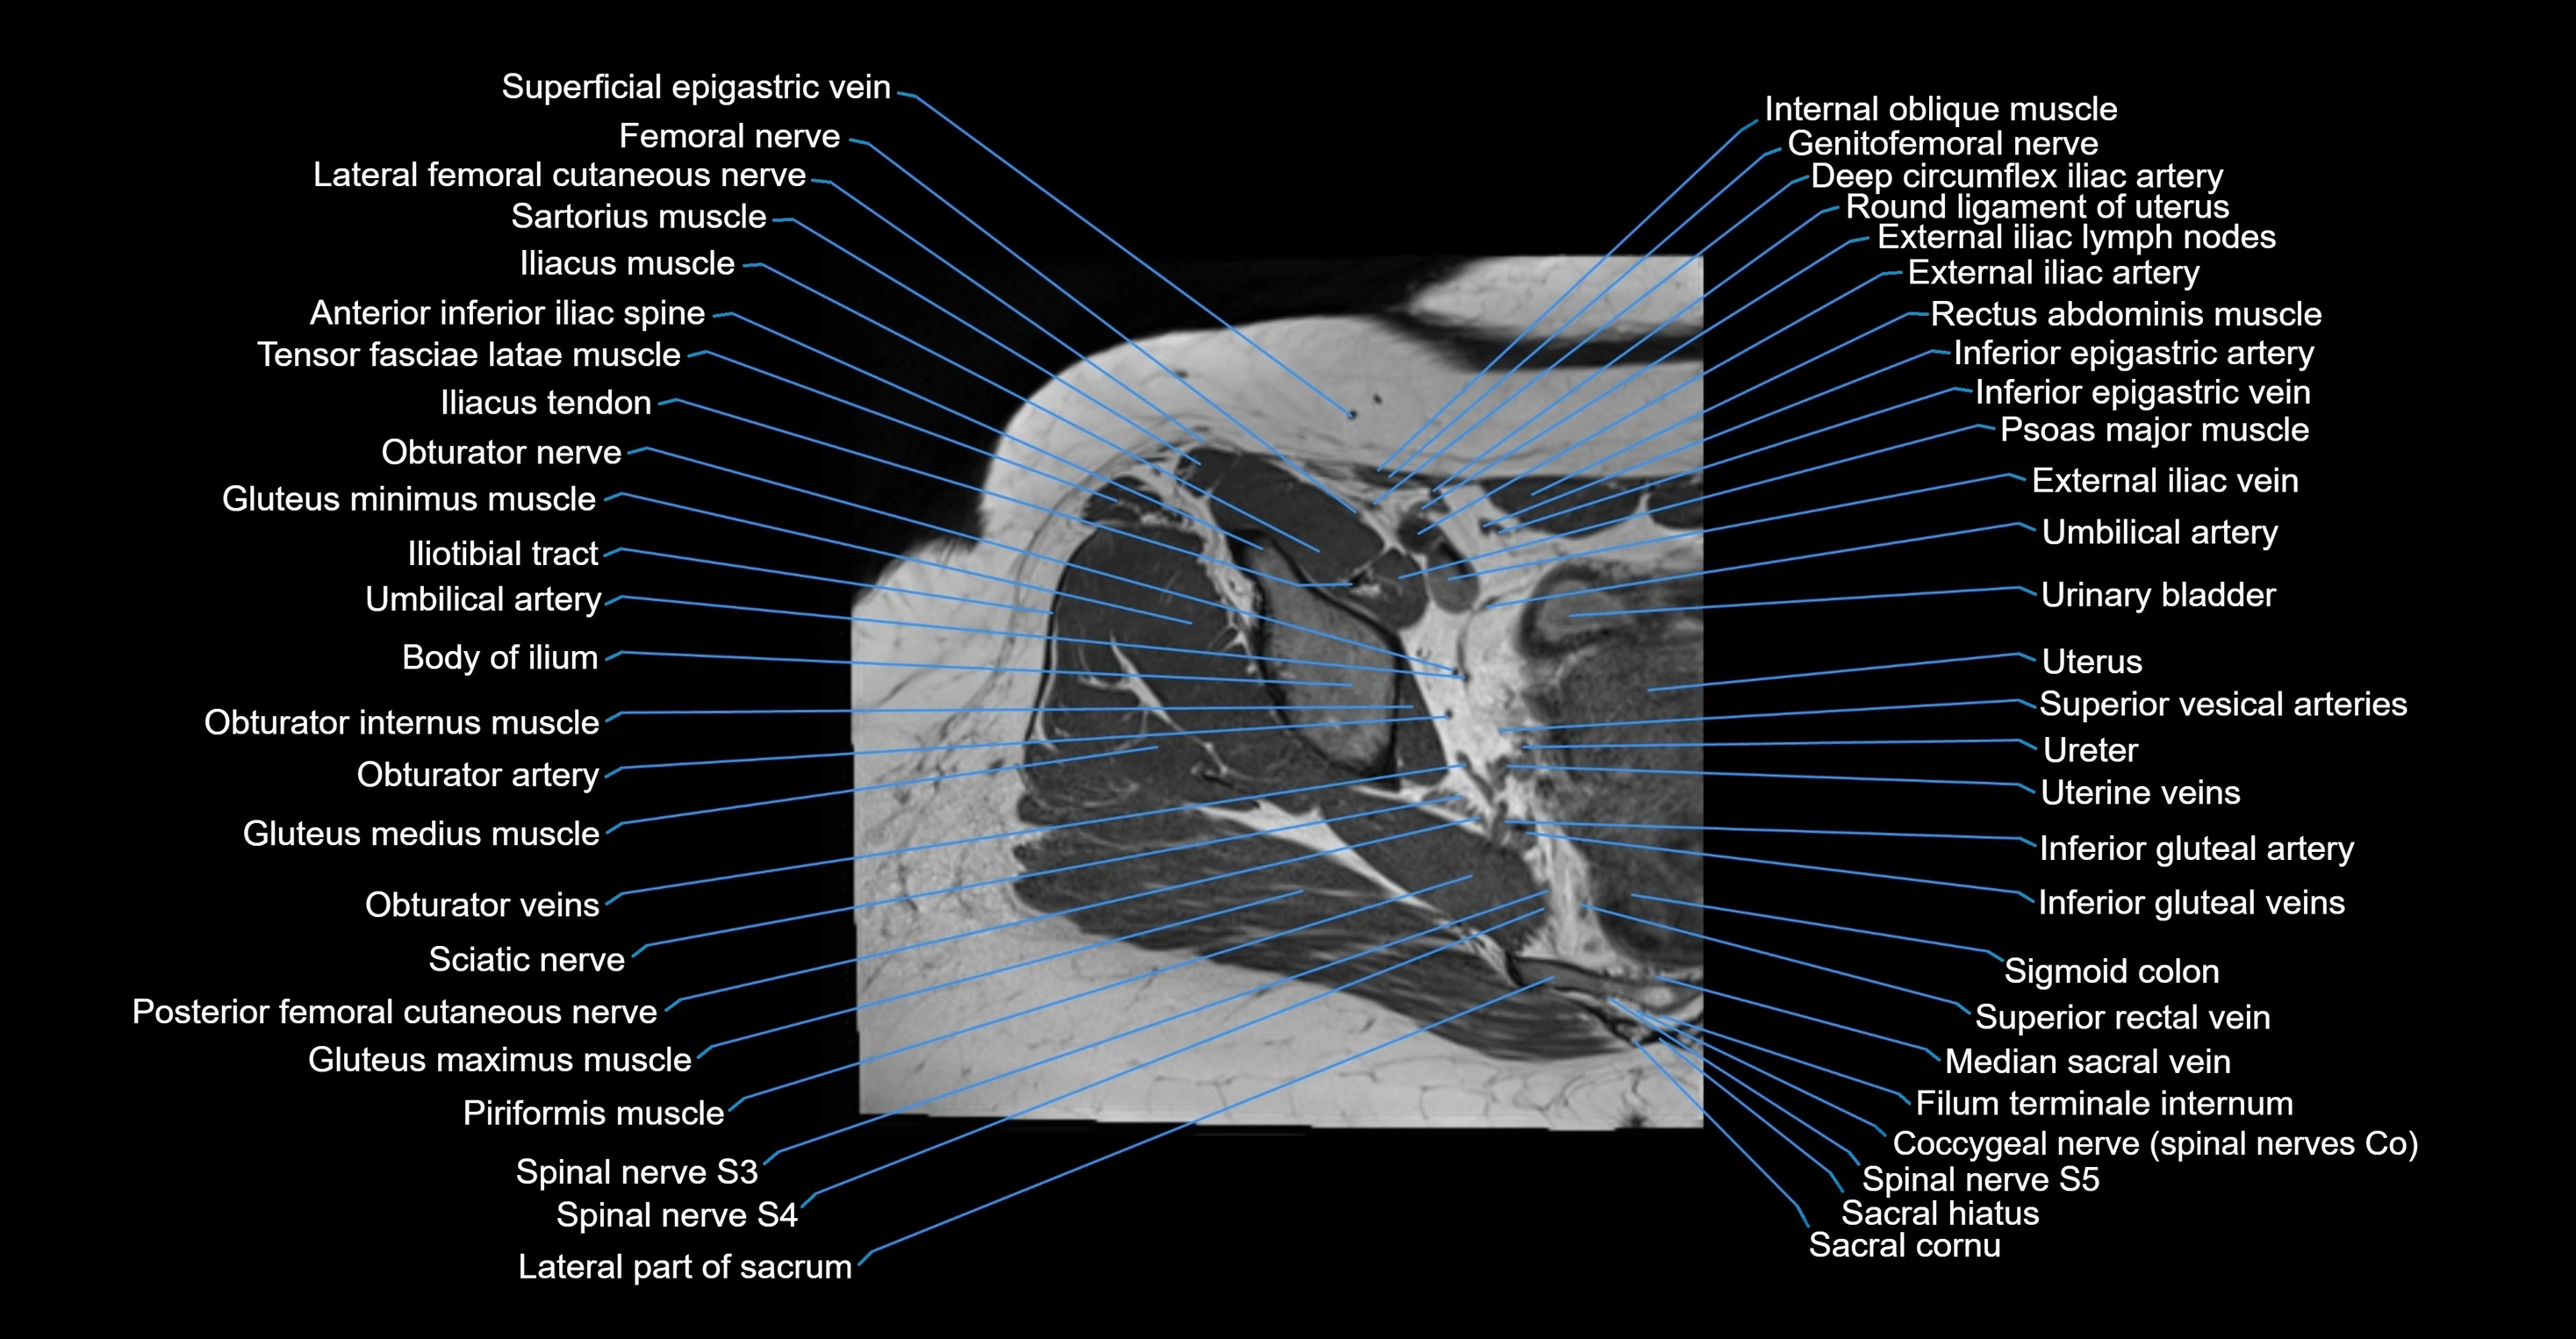

- Anterior inferior iliac spine

- Body of ilium

- Deep circumflex iliac artery

- External iliac lymph nodes

- External iliac vein

- Femoral nerve

- Filum terminale internum

- Genitofemoral nerve

- Gluteus maximus muscle

- Gluteus medius muscle

- Gluteus minimus muscle

- Iliotibial tract

- Inferior epigastric artery

- Inferior epigastric veins

- Inferior gluteal artery

- Inferior gluteal vein

- Lateral part of sacrum

- Median sacral vein

- Obturator artery

- Obturator internus muscle

- Obturator nerve

- Obturator veins

- Posterior femoral cutaneous nerve

- Psoas major muscle

- Round ligament of uterus

- Sacral cornu (sacral horn)

- Sacral hiatus

- Sartorius muscle

- Sigmoid colon

- Spinal nerve S3

- Spinal nerve S4

- Superior rectal vein

- Superior vesical artery

- Tensor fasciae latae muscle

- Umbilical artery

- Urinary bladder

- Uterus